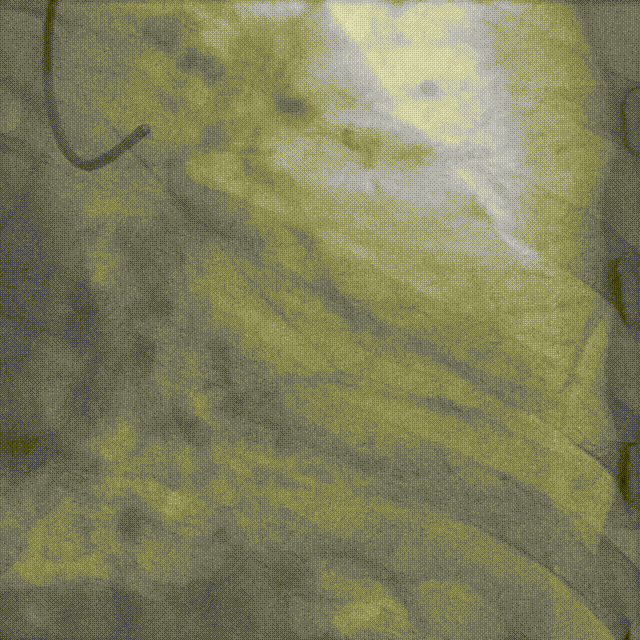

冠脉造影:

▶ LM未见明显狭窄;LAD近中段狭窄60%;LCX未见明显狭窄;RCA细小,未见明显狭窄。